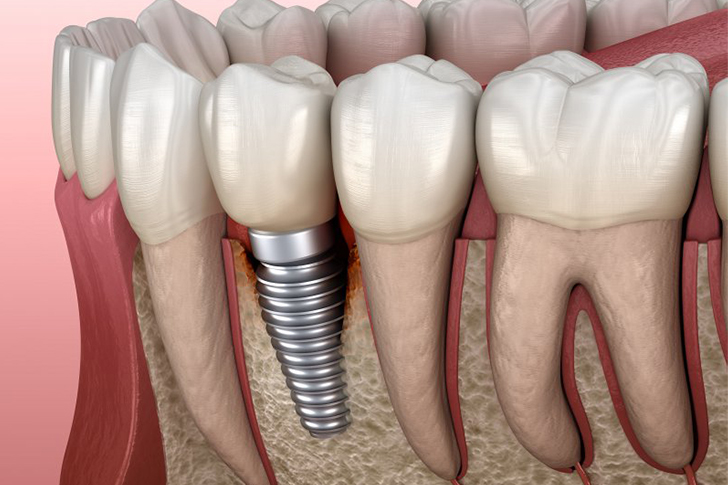

Discover cost-effective dental implant solutions for seniors. This guide covers everything from affordable implants, same-day procedures, and funding options.

- Longevity: Unlike dentures, dental implants are designed to last a lifetime.

- Stability: Provides better stability, which aids in chewing and speaking.

- Bone Health: Helps preserve jawbone structure, preventing further dental issues.

- Single Tooth Implants: Ideal for replacing one missing tooth.

- Bone Density: Adequate bone density is essential for implant success. Bone grafting may be necessary for some seniors.

Full mouth dental implants offer a complete solution for replacing all teeth in the upper and/or lower jaws. While initially more expensive, they can prove cost-effective in the long run due to their durability and low maintenance.

- Initial Consultation: Comprehensive evaluation, including X-rays and possibly CT scans.

- Surgical Procedure: Placement of multiple implants, usually followed by temporary teeth.

- Healing Period: Takes a few months while the implants integrate with the bone.

- Permanent Teeth: Once healed, permanent teeth are affixed to the implants.